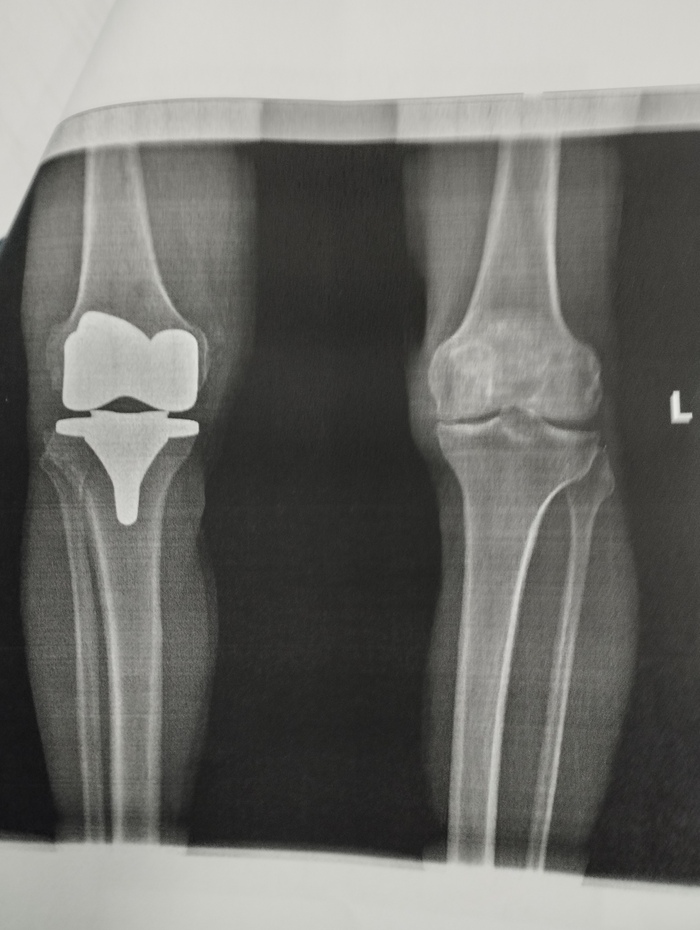

Итак, лет пять-шесть назад начали побаливать коленки, ходил к врачам -ставили артроз. Сначала были таблетки и мази, потом были уколы, в том числе очень дорогущие, которые лично мне особенно никакого улучшения не приносили. В прошлом году делал и уколы собственной плазмой - тоже без эффекта.((( Очень резко ухудшилась ситуация после ковида- такое впечатление, что просто процесс разрушения хряща пошёл лавинообразно. Причём, если в двадцать первом году в левом колене ставили третью степень гонартроза, а в правом вторую, то, к моменту операции, левый сустав как будто не ухудшился, а вот правый прям очень доставлял. Самое главное, что заставило уже не откладывать операцию - в правом колене начались боли независимо от движения, даже в состоянии покоя. Я не мог спать ночью - любое движение приводило к резкой боли, да и без движения были режущие колющие боли.

Почему откладывал операцию до последнего: потому что в двадцать первом году знакомый травмотолог-ортопед сказал, что операция на колене достаточно сложная, так как сустав не простой, шансы на его удачный исход 50/50 и надо пытаться сохранить сустав до последнего. И вот- этот последний момент настал осенью этого года. До этого я много наслушался разных мнений. Но, в основном, сейчас уже все говорили, что операция отработанная, делается во многих местах, а уж в Москве-то вообще практически чуть ли не в каждой больнице. Однако, многие рекомендовали больницу №13 на Велозаводской,(сейчас она филиал №1 больницы им. Демихова), так как там самая старая школа эндопротезирования, поэтому, когда предлагали куда пойти, выбрал её. Раньше такие операции, поскольку они дорогостоящие, и делаются по квоте, надо было ждать продолжительное время. Сейчас ждать практически не приходится, ну -месяц, за это время сдаёшь необходимые анализы и в назначенный день приходишь в больницу. С собой берёшь обычный больничный набор, плюс костыли и эластичные бинты для бинтования ног от тромбов. Единственное - вместо штанов на время госпитализации надо брать шорты! Это важно. Ещё наденьте свободную обувь и возьмите какую-нибудь обувную ложку, чтобы было проще одеваться, когда будете уезжать домой. Не могу сказать что я сильно мандражировал - наверное с возрастом как-то всё притупляется (мне 59). К тому же мне необходимо быть на ногах и нормально ходить, да и измучился. Набор анализов не очень большой- кстати, даже не делали ПЦР на ковид, который, насколько я знаю, до последнего времени при операциях был обязателен. Должны были меня положить в среду утром и днём прооперировать. Но, во вторник позвонили и сказали: если сможете приехать сегодня вечером, то прооперируем вас завтра рано с утра, первым. Я, конечно, согласился, быстро собрался и полетел. На следующий день в 8:00 утра уже лежал голенький в операционной. Очень много я начитался в этих ваших интернетах про операцию, в том числе про то что наркоз не общий, а эпидуральный и, чтобы не слышать как со мной проводят всю экзекуцию, попросил анестезиолога добавить к эпидуралке мне седацию -это когда ты просто спишь во время операции. Ещё важный момент (я сталкивался с этим раньше, когда делал операцию по ушиванию грыжи) - попросил, чтобы мне поставили мочевой катетер, так как первые сутки ты лежишь, а писать очень хочется, в том числе и из-за того что ставят капельницы. И вот тут катетер- это просто какое-то неземное спасение- ты просто не испытываешь позывов в мочеиспусканию, всё само выливается, в противном случае вся процедура с уткой непростая да и двигаться больно. Пока сёстры готовили операционную, побалагурил с ними, потом пришли врачи - укольчик в спину, маску, и я провалился. Но даже сквозь этот медикаментозный сон я слышал, как в меня как будто кувалдой вбивали эти протезы. Кстати о протезах. Много слышал разных мнений о протезах: и то что есть хорошие, но за них надо доплачивать, есть - не ахти, поэтому специально поинтересовался у врача как сейчас обстоит дело. Информация такая: в Москве либо ты делаешь операцию полностью платно, и тогда можешь выбирать протезы любые, в том числе и супер-пупер импортные, по параллельному импорту. Либо ты делаешь по полису, и тогда тебе ставят то, что есть в больнице. Мне сказали, что сейчас в больнице используют китайские протезы, они полные аналоги американских, и считаются хорошего качества. Как сказал врач: во всяком случае лучше отечественных. Итак, после операции привезли в палату, где я часок находился в полусне, потом начал приходить в себя. Очень интересные ощущения от эпидуралки: ты просто не чувствуешь нижней половиной тела, не можешь двигать ногами и, даже, в какой-то момент становится слегка тревожно: блин, а вдруг что-то не так и теперь не сможешь двигаться ... Но, часа через три, начинаешь двигать пальцами ног, а потом полностью возвращается чувствительность. Единственное- нет боли, так как, во-первых, ставят блокаду, а во-вторых, колят обезбол. Конечно нелегко лежать когда не можешь никуда повернуться - очень устаёт спина и всё тело. Через часов 12 отходит блокада и становится больно, но вызываешь сестру -тебе делают укол и боль снимает. Первый обезбол после операции колят промедол, это синтетический аналог морфина, остальные дни уже не наркотик а кеторолак, но тоже хорошо снимает боль. На следующий день после операции (через сутки) снимают мочевой катетер, делают перевязку. Приходит врач-реабилитолог - дают инструкцию ЛФК и уже надо начинать заниматься разработкой ноги. Уже начинаешь вставать и сам костыляешь в туалет. Ещё одно важное замечание - обязательно надо взять с собой влажные салфетки, потому что весь туалет и гигиена происходит с их помощью. Итак, с самого начала врачи говорят, что можно и даже нужно на ногу наступать, а костыли только дозируют нагрузку и дают поддержку. Дело в том, что протезы ставятся на специальный костный цемент, плюс они же с шипами и забиваются в сустав и практически сразу намертво там фиксируются. И действительно - ты достаточно спокойно можешь на эту ногу наступать - боли в суставе нет вообще, - вся боль только от того, что всё-таки делали большой разрез, всё там раскрывали, резали, пилили. Конечно повреждения мягких тканей значительные, и нога очень отёкшая и всё это болит. Точнее, благодаря обезболу не болит, а просто ею пока двигать больно. Именно когда пытаешься её сгибать или поворачивать. Возвращаясь к протезу: там же меняется не весь сустав, а просто спиливают с него верхнюю часть, где был хрящ, и вот туда ставят протез: на картинке видно какой. В общем, уже со второго дня я достаточно бодренько костылял по всему отделению, и даже спускался по лестнице вниз, в приёмное, где стоял кофейный аппарат. Кстати, ходьба по лестнице, входит в программу ЛФК со второго дня. По лекарствам: по сути, кроме обезбола больше ничего не делали. Я удивился, что не стали колоть никаких антибиотиков, наверное это делают если поднимается температура, это означает, что пошло какое-то воспаление . У меня всё было нормально, поэтому мне только кололи обезбол, давали омепразол для желудка и кроверазжижающее. Кстати, обязательно настаивают на том, чтобы компрессионные чулки (или в моём случае эластичные бинты) носились не меньше месяца, и в это же время принимать надо кроверазжижающее, во избежание тромбоза нижних конечностей. Я знаю, что обычно этим все пренебрегают, я постараюсь максимально следовать этому указанию, хотя конечно бинты давят, и это один из неприятнейших моментов послеоперационного периода. Буду заканчивать - уже сам устал писать эту простыню! Выписали меня на следующий понедельник утром, сделав последнюю перевязку и дав выписку и рекомендации. В больницу и обратно свозил меня друг на машине. Дома потихоньку восстанавливаюсь, чуть полегче стало примерно через день: чуть чуть начал спадать отёк и синяк, ну и вообще - дома стены лечат. Но пока нога гнётся очень мало, но делаю упражнения. Мне надо поскорее встать на ноги - мне очень важно ездить на машине. Врачи сказали что через 2.5 - 3 недели, в общем, на машине с коробкой автоматом ездить можно. А вообще, на костылях ходишь полтора месяца, а потом просто ходишь с палочкой месяц. Считается, что через 3 месяца ты абсолютно здоров, а полгода - это вообще абсолютно полная реабилитация. Посмотрю как дела пойдут дальше, - если всё будет хорошо, то через 3-4 месяца сделал бы и вторую ногу, которая тоже в очень плохом состоянии. Спасибо за внимание тем кто осилил, закончен репортаж!))) Если есть вопросы -задавайте, постараюсь ответить. Но, как говорил, не могу делать это часто и быстро.